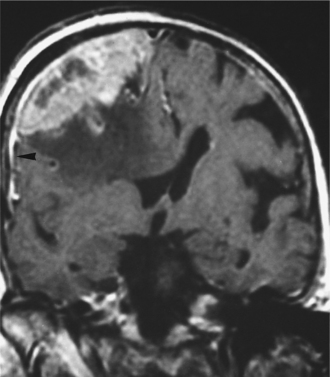

Pathogenesis.: Meningiomas originate in the arachnoid layer of the meninges and are believed to be derived from the cells and vascular elements of the meninges. Cytogenetic analysis has demonstrated multiple deletions on chromosome 22 in most people with meningioma. They are most often located between or over the cerebral hemispheres, at the skull base, or in the posterior fossa. Meningiomas are typically well-circumscribed globular masses. They may infiltrate the dura, the dural sinuses, or bone, but generally do not invade the underlying brain parenchyma. See Figs. 30-8 and 30-9 for CT scans of meningiomas. Most meningiomas grow as well-encapsulated tumors, but others develop in relatively thin sheets along the dura.

Figure 30-8 Meningioma. A, A noncontrasted computed tomographic scan shows a very dense, peripherally based lesion in the left cerebellar area. B, A bone window image obtained at the same level shows that the density is due to calcification within this lesion. (From Mettler FA Jr: Essentials of radiology, ed 2, Philadelphia, 2005, Saunders.)

Figure 30-9 Computed tomographic scan with contrast of a meningioma in a patient who presented with mild cognitive deficits, illustrative of the size a slow-growing tumor can attain in the brain. The tumor was completely resected. (From Goldman LM, Ausiello D, eds: Cecil textbook of medicine, ed 22, Philadelphia, 2004, Saunders.

Meningiomas, because of their proximity to or invasion of the bone, are known to provoke a local osteoblastic response termed hyperostosis. This may cause a profuse local thickening of the skull. Fig. 30-10 shows diffuse reactive hyperostosis as well as facial distortion from the growing meningioma.

Figure 30-10 A, Upper eyelid edema, mild proptosis, and downward displacement of the eye due to en plaque sphenoid wing meningioma. B, Computed tomographic scan of the same patient demonstrating lytic bone lesions and diffuse reactive hyperostosis due to bone infiltration by meningioma. (From Abeloff MD, Armitage JO, Niederhuber JE, et al: Clinical oncology, ed 3, Philadelphia, 2004, Churchill Livingstone.)